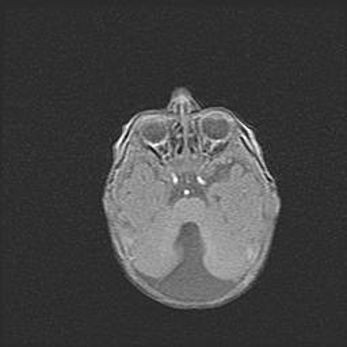

Подострая гематома правой гемисферы мозжечка.

Наружная гидроцефалия.

Возраст: 15 дней

Вес: 3100 г

Пол: женский

Окружность головы: 37 см

Срок гестации: 35-36 недель

При открытой наружной форме гидроцефалии у новорожденных расширяются и переполняются субарахноидные пространства.

Кровоизлияния в мозжечок имеют две клинико-анатомические формы: полушарные гематомы и кровоизлияния в червь.

К появлению этой патологии может привести: повреждения головного мозга, возникающие в результате асфиксии и гипоксии плода при беременности, или травмы во время родов. Редко гематома мозжечка может быть результатом первичной коагулопатии и сосудистой мальформации, диссеминированном внутрисосудистом свертывании, изоиммунной тромбоцитопении.